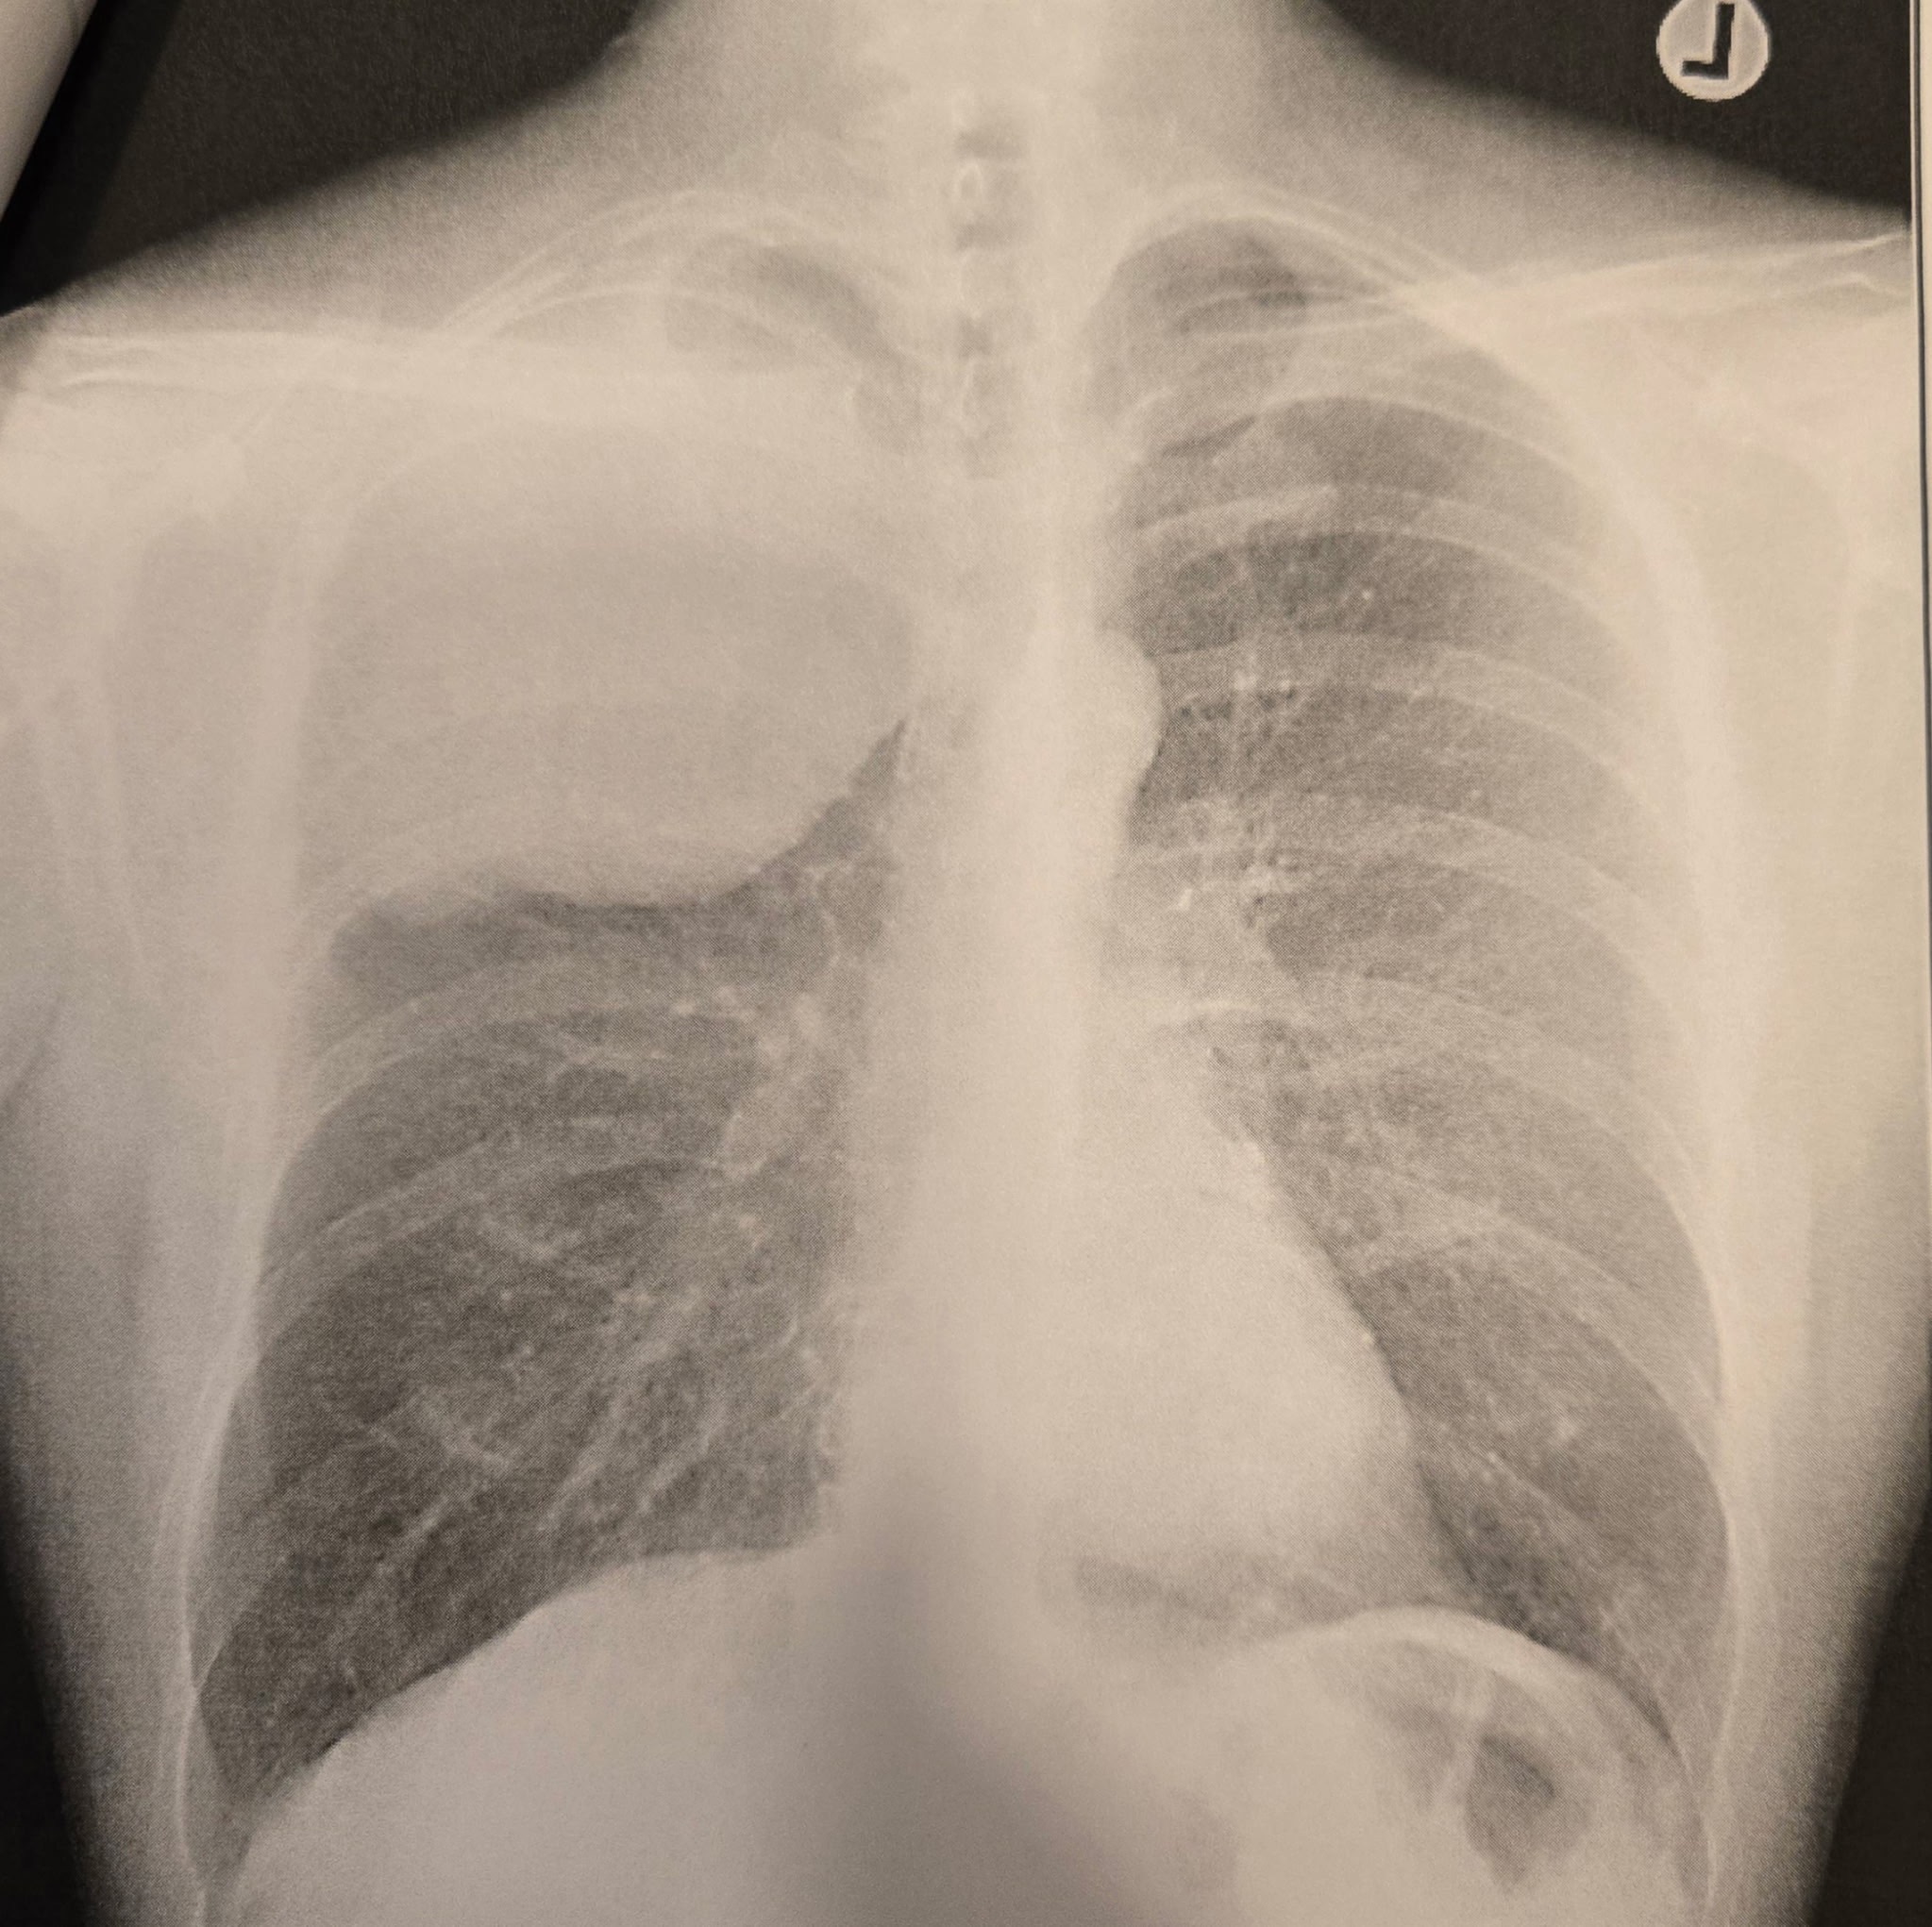

Hi, my name is Angelina and I’m reaching out on behalf of my incredible dad, Raul, and my mom, Cindy. Recently, our world was turned upside down when my dad was diagnosed with Stage 3 Sarcomatoid Lung Cancer — a rare and aggressive form of cancer. This diagnosis came suddenly, and our family is still trying to wrap our heads around what this means. My dad is the strongest, most hardworking person I know. He's always been there for us, and now he needs us more than ever. The road ahead will be difficult.